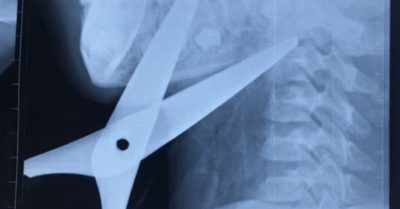

Các y bác sĩ Bệnh viện Nhi trung ương Hà Nội vừa cứu sống bé H. 7 tuổi ở tỉnh Ninh Bình bị kéo đâm xuyên cổ.